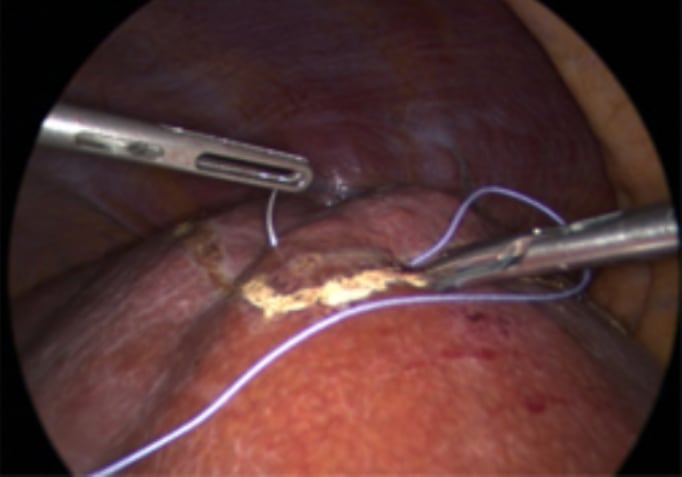

Placement of stay suture

Nonanatomical resection using CUSA